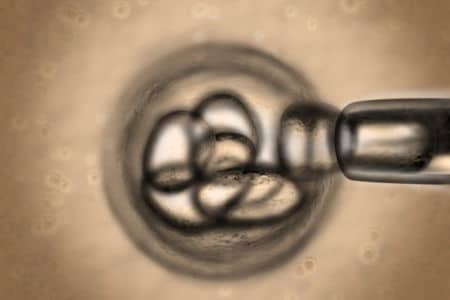

Pene artificiale? Forse poco ci manca. Dai laboratori americani arriva un nuovo importante risultato nel campo della bioingegneria. Tra provette,...